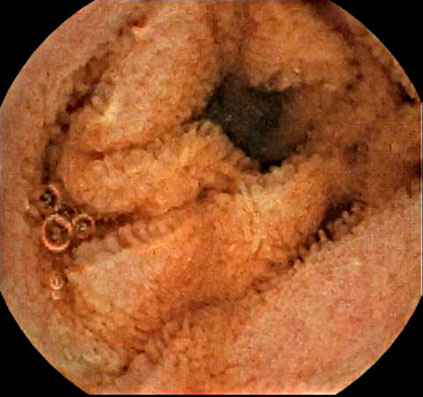

Case Gallery

The new capsule’s enclosure is light and compact, yet harbors an incredible image sensor with increased view angle, more natural toning and detailed image.